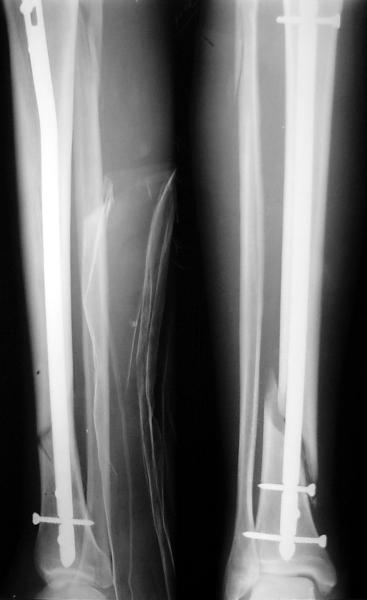

Как мне показать пример? Фото стоящего на одной оперированной конечности пациента? O! Пример, подвигнувший нас на некоторое изменение технологий. Пациент этот ходил с полной нагрузкой вопреки рекомендациям. В качестве подтверждения - сломанный проксимальный статический винт к 1 мес., а к 2 мес. - все остальные. Сейчас мы перешли на более fool-proof остесинтез.

На мой взгляд, на снимках, приведённых Вами - неправильно сростающийся перелом дистальной трети большеберцовой кости, состояние после остеосинтеза интрамедуллярным гвоздём.

Как Вы пишите снимок под номером 1 - менсяц после операции, под номером 2- два месяца после операции.

Вы не послали послеоперационный снимок, поэтому трудно судить о состоянии редукции после операции.

Установка с медиальной стороны гвоздя в области дистального фрагмента дополнительного шурупа помогло бы Вам репонировать и удержать перелом в анатомическом положении, предотвратило варусную деформацию и смещение по ширине.

Пример, приведённый Вами в нашей дискуссии по времени нагрузки после остеосинтеза не совсем удачный... Ваш больной имеет счастье, что первым согнулся проксимальный замыкающий винт, а не дистальный и гвоздь не пенетрировал голеностопный сустав.

I think that the X-Rays show S/P IMN of Spiral # of the Distal Tibia consoles in misalignment.

You wrote that a picture number 1 - f month after the surgery, and number 2-two months after the surgery.

You have not sent a postoperative X-Rays; so it's impossible to discuss about the condition of a reduction after operation.

Let to express concerning technique of operation my opinion... Insertion of a screw to medial side of a nail in distal fragment would help you to reduction and to keep this fracture in anatomic position has prevented varus deformity and displacement on width. By the way, if it is possible send a postoperative picture.

Your patient is lucky enough, that by the first was bent proximal locking screw, instead of distal and a nail does not penetrate to the ankle joint.

Это наглядная демонстрация возможности ранней полной нагрузки при нестабильном по оси повреждении, причем не в самых благоприятных механических условиях - при плохом сопоставлении, со слабым фиксатором.

Сверху - один статический винт, а снизу - три. Что раньше сломается? Конечно, он потом и нижние сломал, и Вы правы, если бы верхний динамичесий винт уже уперся бы в нижний край отверстия, будь гвоздь подлинее, перфорировал бы сустав как пить дать.